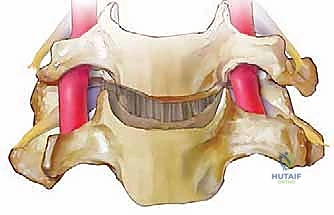

الخطوة 6: زراعة الطعم العظمي (Bone Graft Insertion)

بعد إزالة القرص، تتبقى فجوة بين الفقرتين. لمنع انهيار هذه المسافة ولتحفيز التحام الفقرتين معاً، يتم إدخال "طعم عظمي" أو قفص صناعي (Cage) مصنوع من مادة PEEK أو التيتانيوم ومملوء بمادة عظمية.

الخطوة 7: التثبيت المعدني (Instrumentation)

لضمان الاستقرار الفوري ومنع حركة الطعم العظمي حتى يكتمل الالتحام (والذي يستغرق أشهراً)، يقوم الدكتور هطيف بتثبيت شريحة معدنية صغيرة من التيتانيوم على الجزء الأمامي من الفقرتين باستخدام براغي دقيقة.